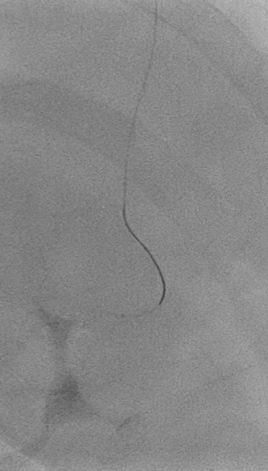

PCI was conducted using guide catheter EBU3.5/6F, A 0.014-inch floppy guidewire and was placed in distal LAD. After sliding the distal lesion with semicompliant 1.5 x 15mm, we encountered distal perforation type V with Ellis type III. Multiple prolonged ballon inflation was done using semicompliant 2.0 x 15mm at 4 atm but the perforation jet persisted. We decided to do microcatheter-assisted absorbable suture embolization technique with chromic catgut 3.0. The perforation was successfully managed. Echocardiography evaluation revealed Concentric Left Ventricular Hyperthrophy with normal LVEF without signs of pericardial effusion. Patient was dismissed from hospitalization without further complication.